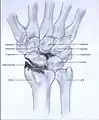

- Stage III: the osteoarthritis is localized in the entire radioscaphoid joint with involvement of the capitolunate joint.

Stage III

In Stage III wrist osteoarthritis, some surgeons offer patients proximal row carpectomy and interpose some of the wrist capsule to account for the arthritis in the capitate. Four-corner arthrodesis, as described above in stage II, is also an option.